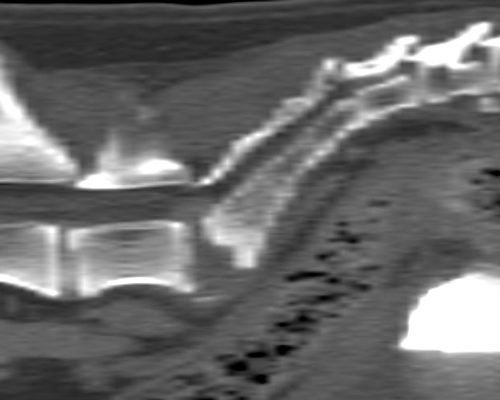

TC MULTISTRATO